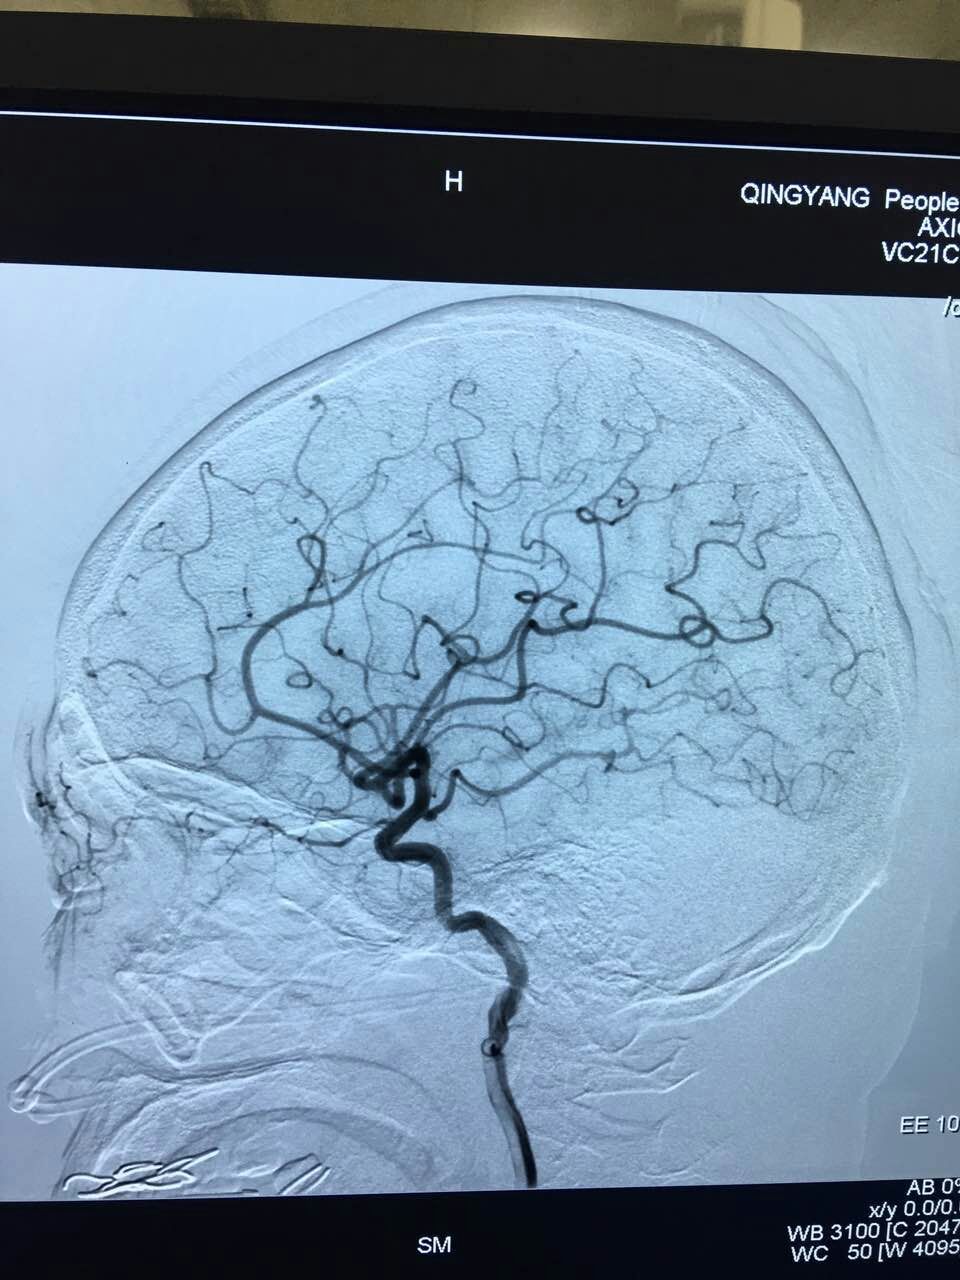

六、神经外科微创与介入诊疗。(一)神经内镜辅助下的显微神经外科手术是精准医疗的一项关键技术,在神经内镜辅助下借助于内镜的照明系统和显示系统,完成以前术中难以发现的死角和高难度手术,大大降低了脑出血患者和颅内肿瘤患者的死亡率和致残率。(二)脑血管造影及介入治疗,通过脑血管造影了解脑血管形态,进一步发现颅内动脉瘤、血管畸形、血管狭窄等病因,采取相应治疗措施如颅内放置血管支架、动脉瘤栓塞、血管成型术或开颅行动脉瘤夹闭等。微创神经外科与介入治疗的开展实施,在庆阳市脑血管疾病、颅内肿瘤等疾病诊疗方面开辟了新天地。